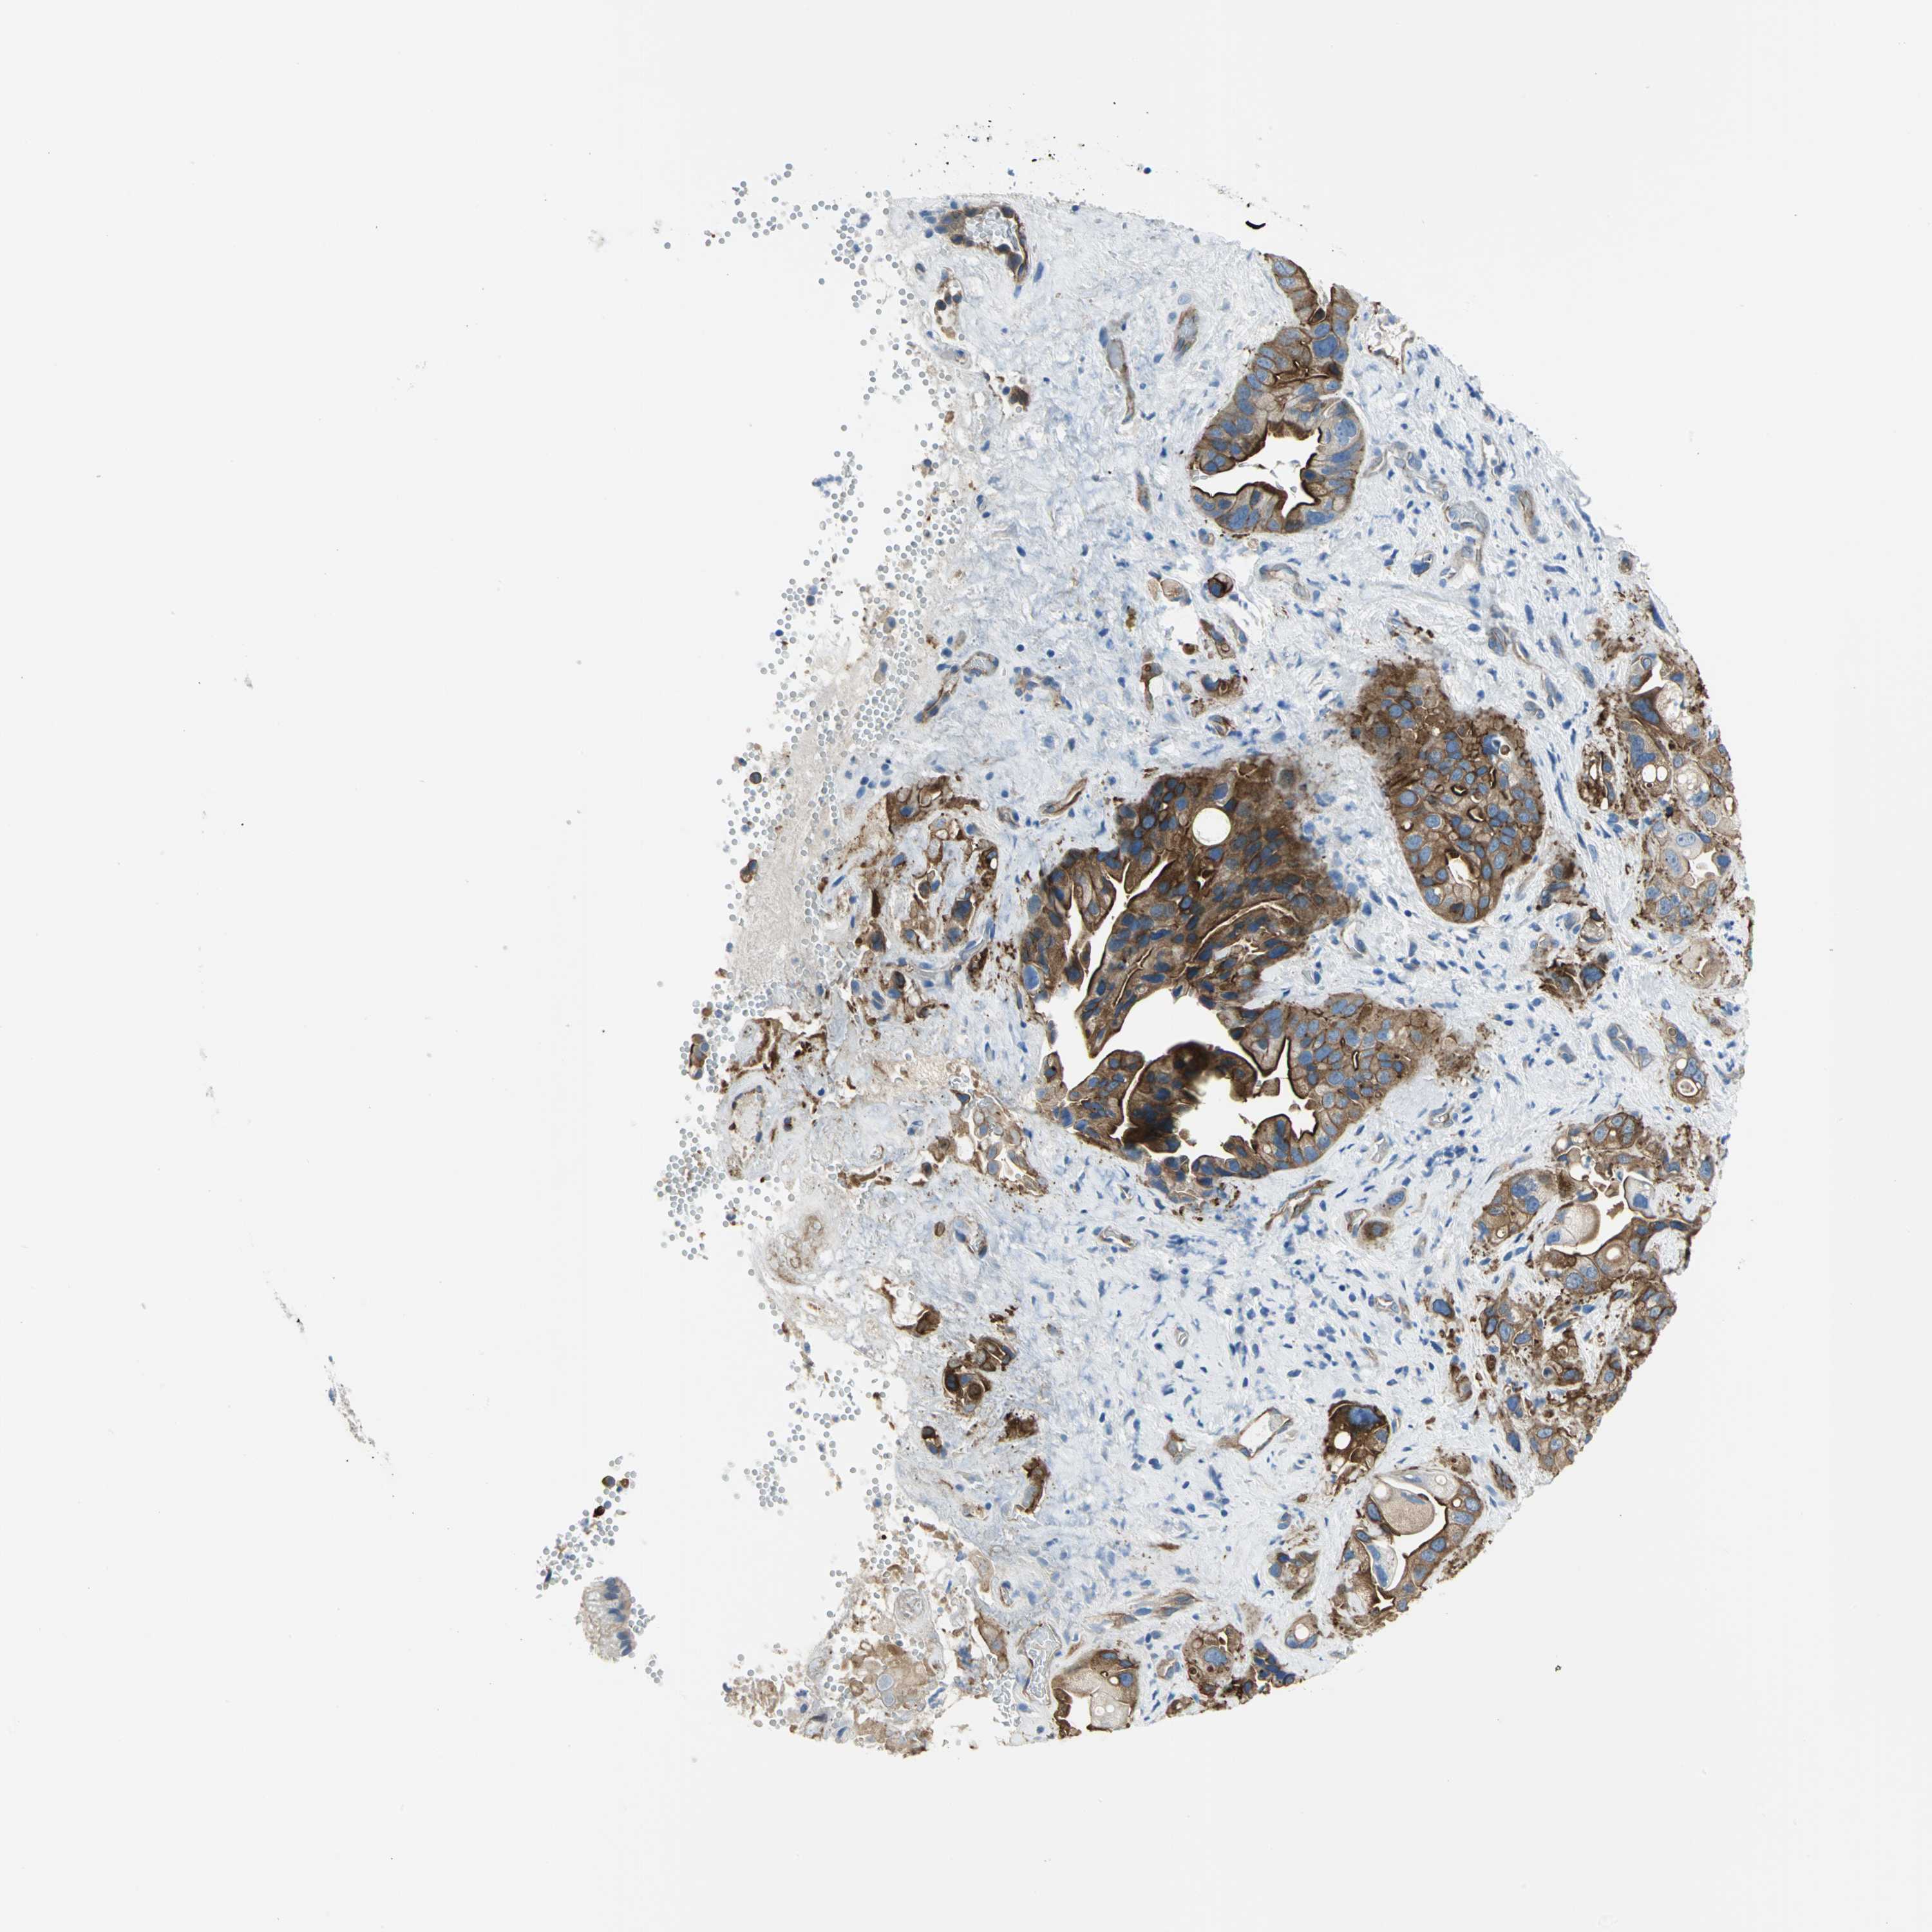

PANCREATIC CANCER - Protein expressioni

A mouse-over function shows sample information and annotation data. Click on an image to view it in a full screen mode. Samples can be filtered based on level of antibody staining by selecting one or several of the following categories: high, medium, low and not detected. The assay and annotation is described here.

Note that samples used for immunohistochemistry by the Human Protein Atlas do not correspond to samples in the TCGA dataset.

Antibody stainingi

Antibody staining in the annotated cell types in the current human tissue is reported as not detected, low, medium, or high, based on conventional immunohistochemistry profiling in selected tissues. This score is based on the combination of the staining intensity and fraction of stained cells.

Each image is clickable and will lead to virtual microscopy that enables deeper exploration of all samples and also displays staining intensity scores, fraction scores and subcellular localization as well as patient and tissue information for each sample.

Antibody HPA004747

Antibody HPA004886

Antibody CAB019322

Adenocarcinoma, NOS

Adenocarcinoma, metastatic, NOS